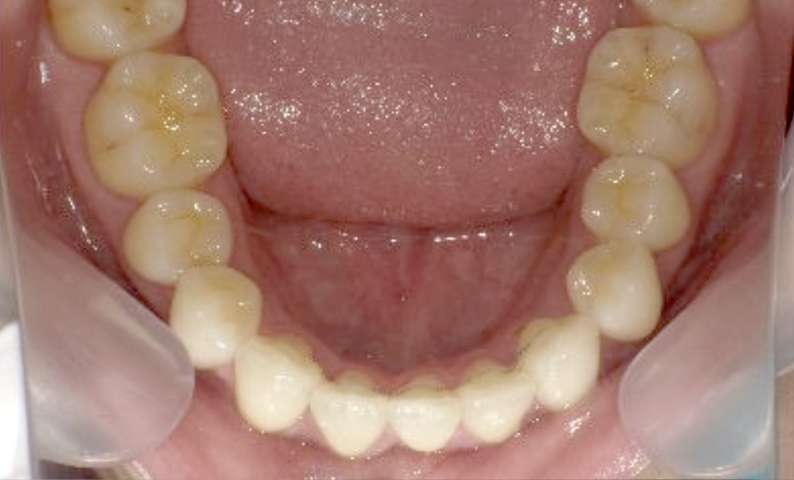

症例_004 下顎だけの部分矯正

治療期間:7ヶ月金額:24万円+税男性前歯のガタガタ下の前歯だけ